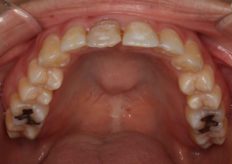

Before

右の前歯が前に出ているのが気になるとの事で来院されました。32

上の前歯だけで治療したいとのことが希望と転職するのでそれまでに出来るだけ早く終わらせたいとのことでした

検査ををすると下の前歯が少し前に出ているので上の前歯だけではこの歯に当たって綺麗に並ばない事が判り下の前歯も治療することを提案し上下前歯部の治療を行うことにしました。

期間をできるだけ短くとのことですので検査後2週間から治療が始めれる歯の表面にブラケット装置をを付けるダイレクトボンデングにて行いました、

並べた歯が前に出ないように歯と歯の間を少しずつ削るIPRを行い治療を行いました、期間は少しかかりましたが綺麗な歯並びになり満足いただけました。